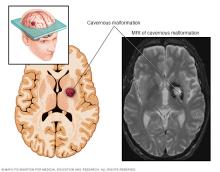

A cerebral cavernous malformation is an irregularly formed blood vessel, shaped like a small mulberry. It can form in the brain or spinal cord and may result in a wide range of neurological symptoms.

Cerebral cavernous malformations (CCMs) are groups of tightly packed, irregular small blood vessels with thin walls. They may be present in the brain or spinal cord. The vessels contain slow-moving blood that's usually clotted. CCMs look like small mulberries. In some people, CCMs can cause blood to leak in the brain or spinal cord.

CCMs vary in size. Often they are less than half an inch (1 centimeter). Most CCMs are sporadic. This means the CCM occurs as a single cavernous malformation and there isn't a family history. But about 20% of CCMs affect people of the same family. These are known as familial CCMs. Familial CCMs are related to a gene change passed down through families. People with familial CCMs usually have multiple cavernous malformations.